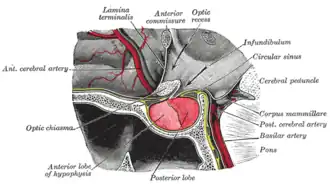

A glândula pituitária ou hipófise é chamada, frequentemente, de "glândula mestra" do corpo humano. Parte do eixo hipotálamo-hipófise, ela controla inúmeras funções endócrinas no organismo, através da liberação de vários hormônios no interior do sistema circulatório. A hipófise se localiza inferiormente ao cérebro, em uma depressão (fossa) do osso esfenoide conhecida como sela túrcica. Apesar de estar anatômica e funcionalmente conectada ao cérebro, a glândula pituitária é envolvida pela dura-máter e está fora da barreira hematoencefálica. Ela está separada do espaço subaracnóideo pelo diafragma da sela, logo a aracnoide e o fluido cerebroespinal não podem acessar a sela túrcica.

A hipófise é dividida em dois lobos, o lobo anterior, que compreende dois terços do volume da glândula, e o lobo posterior (um terço do volume), separados entre si pela pars intermedia.

O lobo posterior (lobo neural ou neuroipófise) da glândula pituitária não é, apesar do nome, uma glândula verdadeira. O lobo posterior contém axônios de neurônios que se estendem do hipotálamo, com o qual está conectado pelo talo hipofisário. Os hormônios vasopressina e ocitocina, produzidos pelos neurônios dos núcleos supraóptico e paraventricular do hipotálamo, são armazenados no lobo posterior e liberados nas terminações axônicas (dendritos) localizadas no lobo.